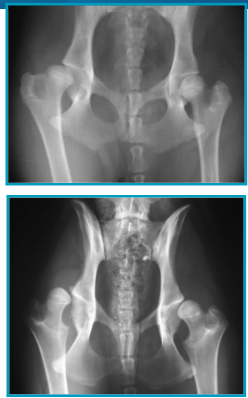

How is radiography done for hip dysplasia?

How can we assess level of hip sub/luxation from radiographic images?